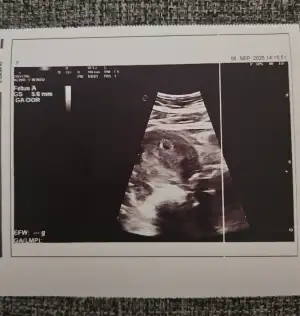

Kızlar gittim doktora karından baktı. Keseyi gördük daha çok küçük. 😍😍😍

Merhabalar, çok şükürler olsun ki keseyi gördük minicik ☺️ Doktorum lekelenmenin 10 gebenin 6’sında görüyoruz dedi, ağrılar batmalar için de gayet normal olduğunu söyledi. Duphaston reçete etti onu kullanacağım. İyi gelir inşallah 🙏🏻